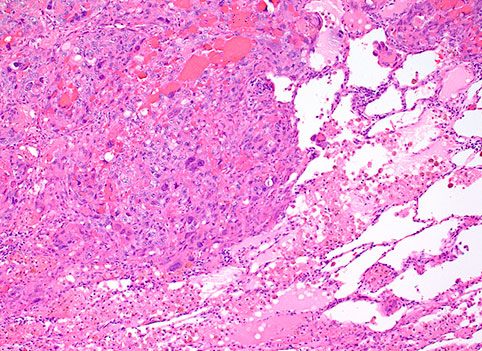

С диагностической целью может быть проведено цитологическое исследование выпота, но очень часто результаты этих исследований сомнительны. Поэтому «золотым» стандартом является гистологическое исследование, включая иммуногистохимическое исследование.

Плевроскопия, видеоассистированная торакоскопия или открытая биопсия плевры, после удаления плеврального выпота, могут быть необходимой процедурой для получения достаточного материала, с целью точного гистологического диагноза. Существует три основных гистологических типа (эпителиальный, саркоматоидный и смешанный), при этом на долю эпителиального типа приходится около 60 % всех мезотелиом.